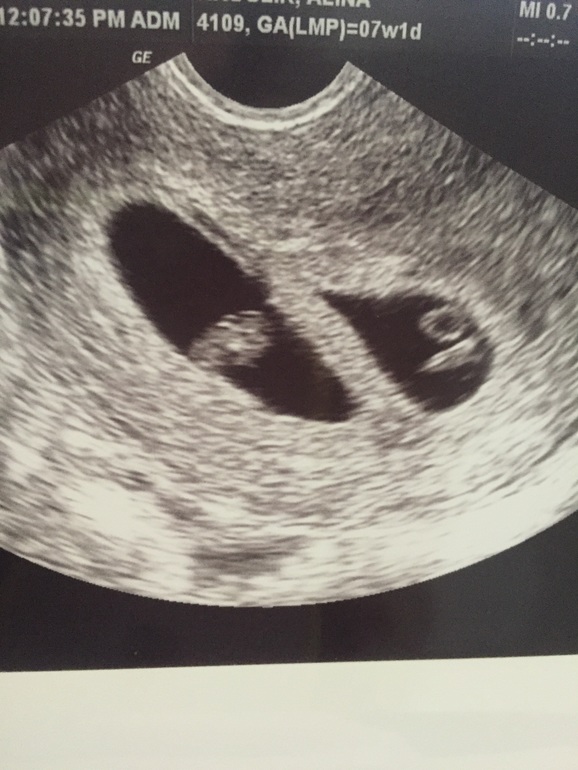

Господи!!! Двойня!!!!! 👶🏼👶🏼

Многоплодная беременностьПервое УЗИ 7+1. У нас двойня!!!!!! Ааааааааа!!!!!! Вот почему мой хгч меня так насторожил!!!!!! Девочки, я в полном шоке! Руки трясутся, голова кругом!!!!! Это так волнительно и страшно! У кого из вас двойни? Очень тяжело было? Миленькие, поделитесь опытом 😘 У меня сейчас сердце лопнет!!!!! ❤️❤️